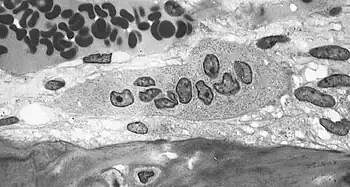

An osteoclast is a large multinucleated cell and human osteoclasts on bone typically have four nuclei[5] and are 150–200 μm in diameter. When osteoclast-inducing cytokines are used to convert macrophages to osteoclasts, very large cells that may reach 100 μm in diameter occur. These may have dozens of nuclei, and typically express major osteoclast proteins but have significant differences from cells in living bone because of the not-natural substrate.[6][7] The size of the multinucleated assembled osteoclast allows it to focus the ion transport, protein secretory and vesicular transport capabilities of many macrophages on a localized area of bone.

In bone, osteoclasts are found in pits in the bone surface which are called resorption bays, or Howship's lacunae. Osteoclasts are characterized by a cytoplasm with a homogeneous, "foamy" appearance. This appearance is due to a high concentration of vesicles and vacuoles. These vacuoles include lysosomes filled with acid phosphatase. This permits characterization of osteoclasts by their staining for high expression of tartrate resistant acid phosphatase (TRAP) and cathepsin K. Osteoclast rough endoplasmic reticulum is sparse, and the Golgi complex is extensive.[8][9][10]